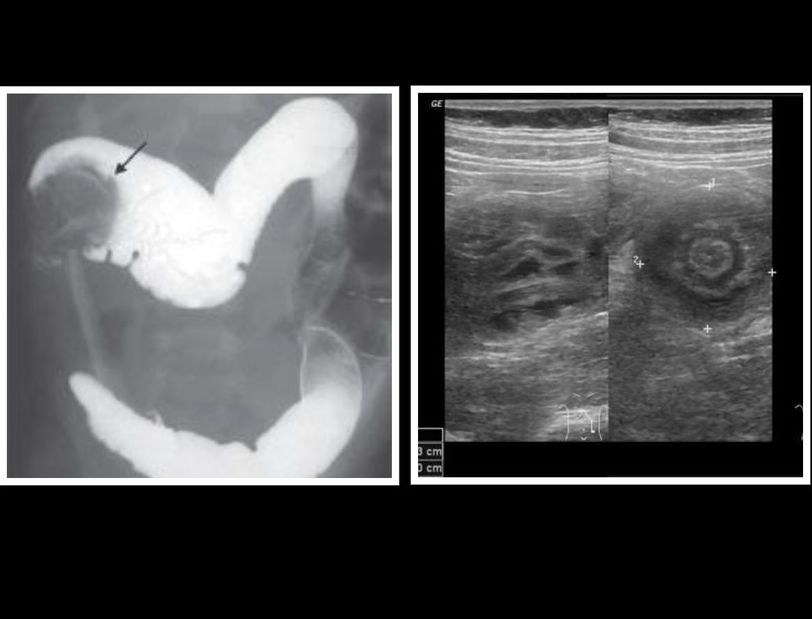

The left image shows CLAW SIGN after a barium enema whereas the right image reveals DOUGHNUT or TARGET SIGN on ultrasound. Both these radiographic findings can be seen in a condition called intusussception. In this condition, a segment of bowel slides into the lumen of the adjacent bowel. It may occur either due to the presence of a pathological entry point such as duplicated intestine or polyp, or it may be associated with intestinal malrotation. The child presents with constipation and on abdominal examination, a sausage shaped swelling may be palpated with convexity facing the umblicus. The right iliac fossa may be empty on palpation. There may be a history of passage of red currant jelly like stool. The ultrasound reveals target or doughnut sign which is actually an intestinal loop within loop. Barium enema reveals claw sign at the site where intusussception has occurred. Image credits: https://radiopaedia.org/cases/intussusception-transient-small-bowel?lang=gb https://www.jaypeedigital.com/book/9789385999000/chapter/ch4